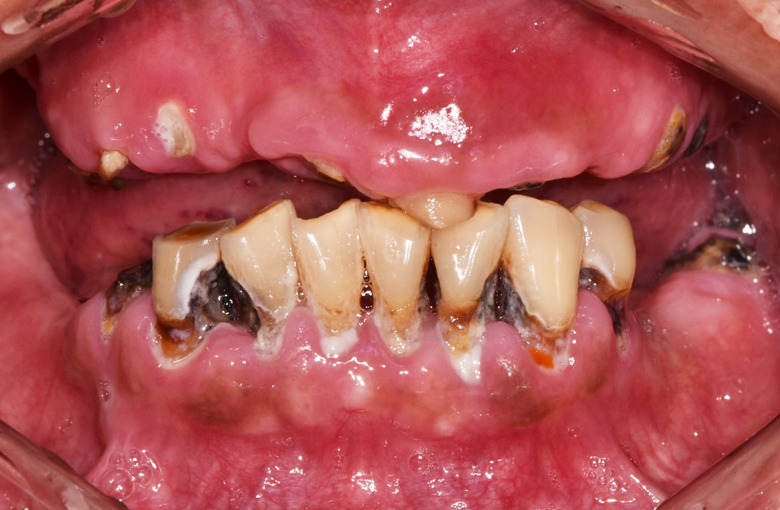

80대 환자분으로, 전체틀니를 사용 중이셨는데 아래 틀니가 자주 잇몸에서 떨어져 불편함을 호소하셨습니다.

치료 전

60대 환자분으로, 최소 비용으로 전체 치아를 만들고 싶다고 하셨습니다. 전체 틀니를 하는 경우가 최소비용으로 치료할 수 있는 방법이나 아래쪽 틀니를 아무리 잘 만든다 하여도 항상 움직이는 혀와 틀니를 받혀주는 잇몸뼈가 부족해서 사용할 때마다 불편감이 클 것으로 예상되었습니다.